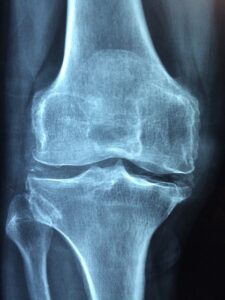

– Imaging tests like X-rays or MRIs to visualize joint damage and rule out other conditions.